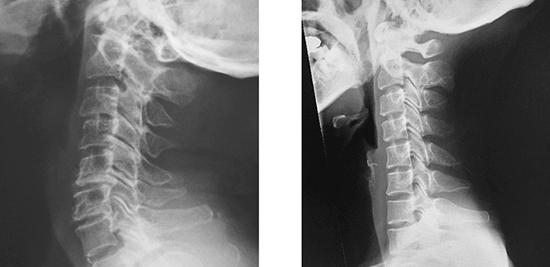

- X선 검사 : 경추부의 X-ray 촬영을 통해 경추의 배열 상태를 확인합니다. 이는 목의 전만 각도와 같은 신체의 구체적인 자세를 평가합니다. 비정상적인 각도가 발견되면 거북목으로 진단할 수 있습니다.